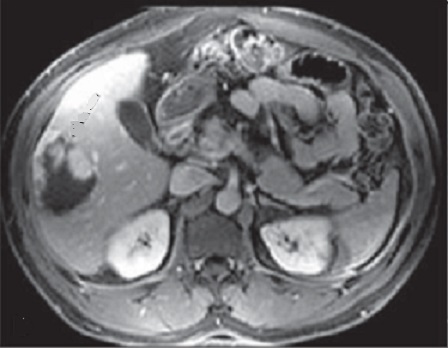

Image

radiologique IRM de kyste du foie : Image lesionel arrondie

ou ovalaire hyposignal en T1 et hypersignal en T2 et nette sủr

T1 + gadolinium FS

Image ỈRM ponderation T1

en coupe axiale d'une kyste simple du foie gauche ,avec

aspect lesionaire ovalaire a hyposignal situe au foie gauche

|

Meme cas

en ponderation T2 : Image lesionnel est tres hypersignal

situe au foie gauche |

Aspect de ce cas ponderee en

T1 + gadolium FS : Image ovalaire a hypodense du foie

gauche |